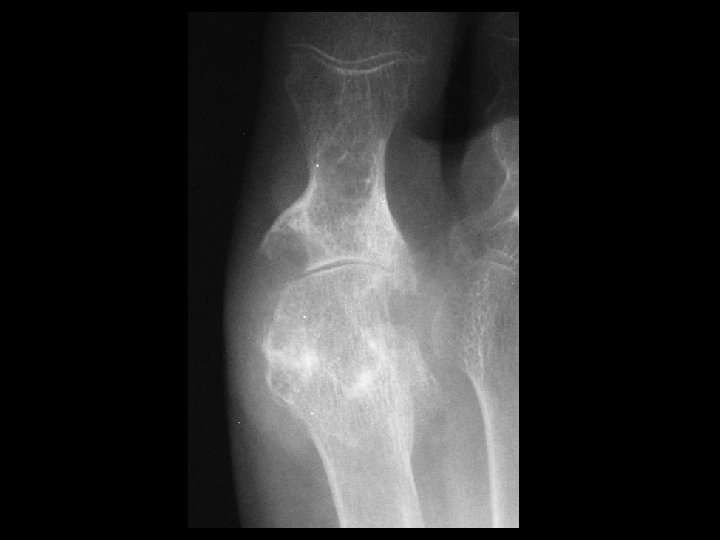

Hemophilia & secondary osteoarthritis • Findings: – severe secondary OA – flared metaphyses – widening of intercondylar tunnel – dense joint effusion • ddx: – JRA